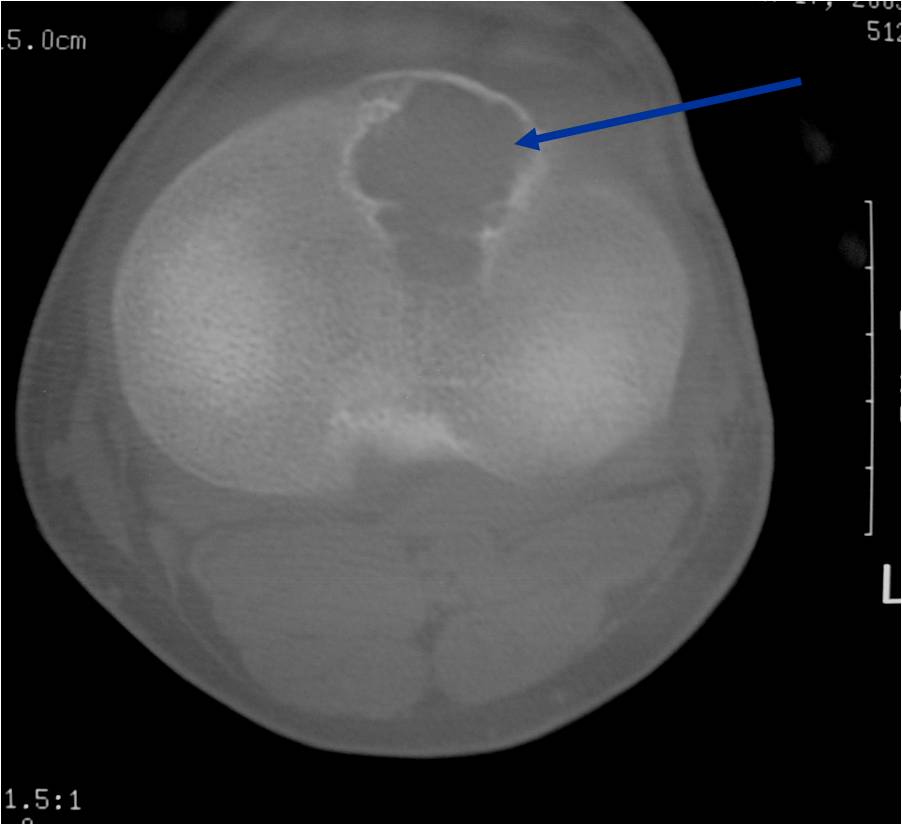

- (CT appearance)

- Most useful for detecting subtle mineralization not apparent on X-rays

- Useful for identifying intact periosteum around any expansile soft tissue component

- surrounding thin reactive shell of bone/mineralization (Egg Shell Rim of Calcification)

- helps place the tumor in a benign category

- helps evaluate:

- bony quality

- extent of bone and cortical destruction

- whether the subchondral plate of bone adjacent to the articular cartilage has been destroyed or is intact